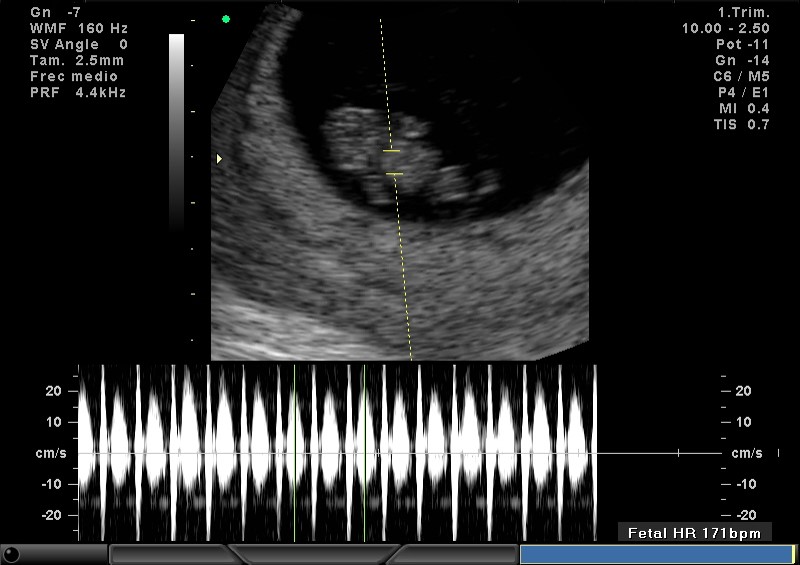

2D FRECUENCIA CARDIACA 10.5 SEMANAS